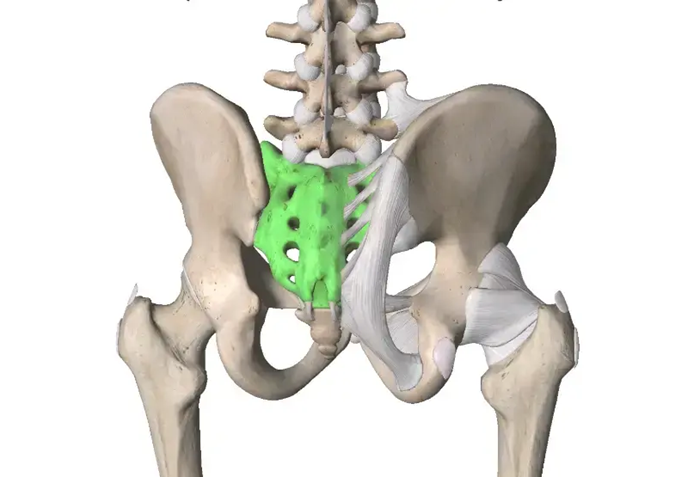

Что показывают снимки крестцово-копчикового отдела

Профессиональный рентгенолог на них может рассмотреть все костные структуры крестцово-копчикового отдела и изменения в них. Это позволяет диагностировать:

- Остеомиелит.

- Вывих и перелом позвонков.

- Надрыв и разрыв межпозвоночных хрящей.

- Наличие у копчика отрыва от основного сочленения.

- Появившиеся первичные новообразования.

- Патологические изменения, свидетельствующие об остеохондрозе и аномалиях в костных структурах.